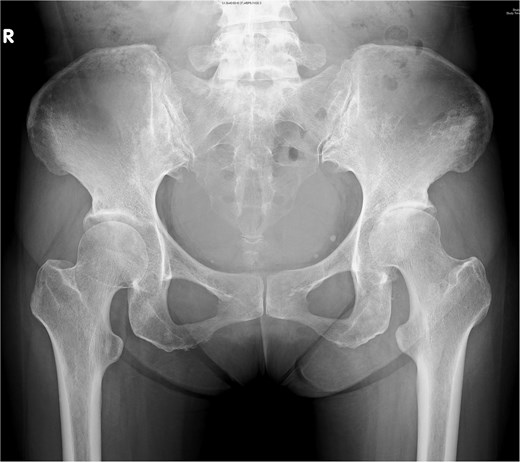

Graphical depiction of a psoas abscess (*) following dissection from the abdominal wall, fascia layers (Camper’s and Scarpa’s fascia), external oblique aponeurosis, and transversalis fascia with medial retraction of the external iliac vessels.